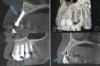

Natylka Опубликовано 30 января, 2010 Поделиться Опубликовано 30 января, 2010 Прошу специалистов посмотреть мой снимок. Имплантат установлен 24 ноября. Беспокоят ноющие боли, помогает УВЧ, но потом спустя пару дней боль начинается снова. Внешне все спокойно, покраснения нет, десна не заросла, заглушка конактирует с полостью рта. Ссылка на комментарий

ВИТА Опубликовано 31 января, 2010 Поделиться Опубликовано 31 января, 2010 по снимку - такое впечатление, что лунка была подготовлена для импланта большего размера....есть вероятность, что имплант не стабилен в лунке, поэтому скорее всего не приживется... Ссылка на комментарий